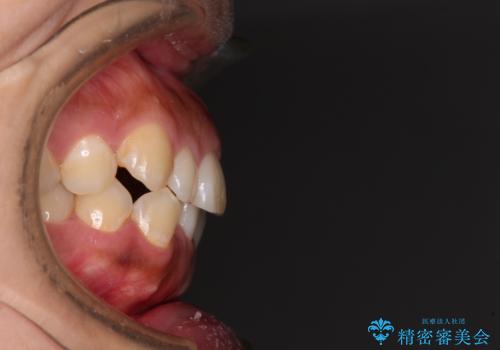

- 前歯の叢生と八重歯を気にして来院された患者様です。

インビザライン単体で改善することも可能ですが、八重歯とその後方にある歯列を確実移動させないと、上下正中がずれてしまう可能性があります。

インビザライン単体での治療ではなく、カリエール・ディスタライザーという補助装置を併用して、より確実性を上げることとしました。

補助装置で八重歯を解消しながら、並行してインビザラインで歯列を整えることとしました。

カリエールディスタライザーを併用したことで、すっきりとした口元になり、上下の正中を合わせることができました。